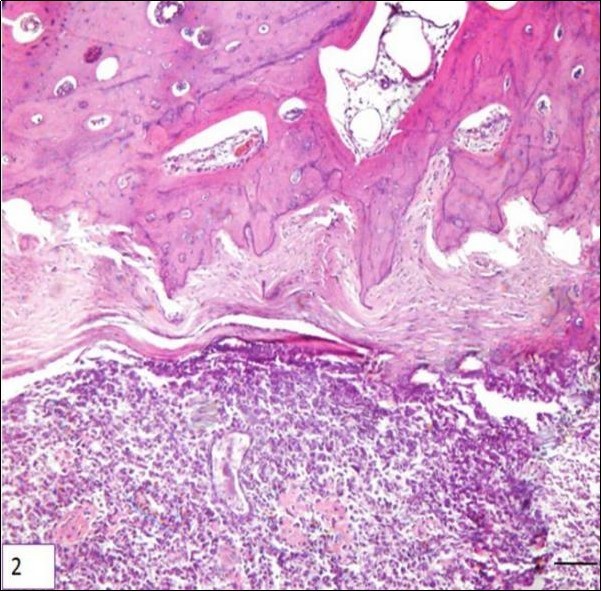

Two types of periosteal osteosarcoma have been described in dogs. The first is an aggressive tumor with the same histopathological characteristics and biological behavior of central osteosarcoma. Such tumors may actually be central osteosarcomas that arose in the cancellous bone of the metaphysis of a long bone and for some undetermined reason developed an eccentric growth pattern. The second type of periosteal osteosarcoma is similar to the description found in humans. Only two reports have been described this tumor in the metaphyseal surface of long bones rather than the diaphyseal surface in humans. Both of them, produce dense bone matrix and none of the dogs had metastasis after limb amputation Figure 217.

Figure 2.Photomicrography of a sample of canine bone (tibia) showing neoplastic mesenchymal proliferation, originated in bone cells, HE. Periosteal array of tumor cells, bar 200 μm.